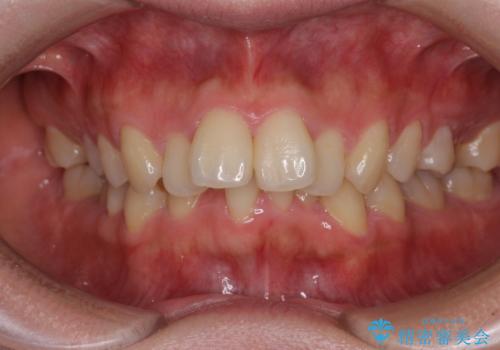

銀歯を白くしたい 一緒に矯正治療も行ない美しい口腔内に